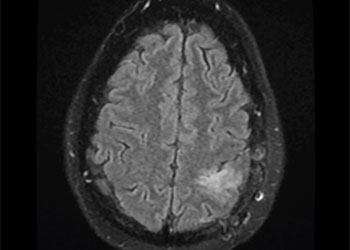

Brain:

Cerebral Metastases from Non-Small Cell Lung Cancer

Author: Xavier P. J. Gaudin D.O., F.A.C.O.S., Read More!